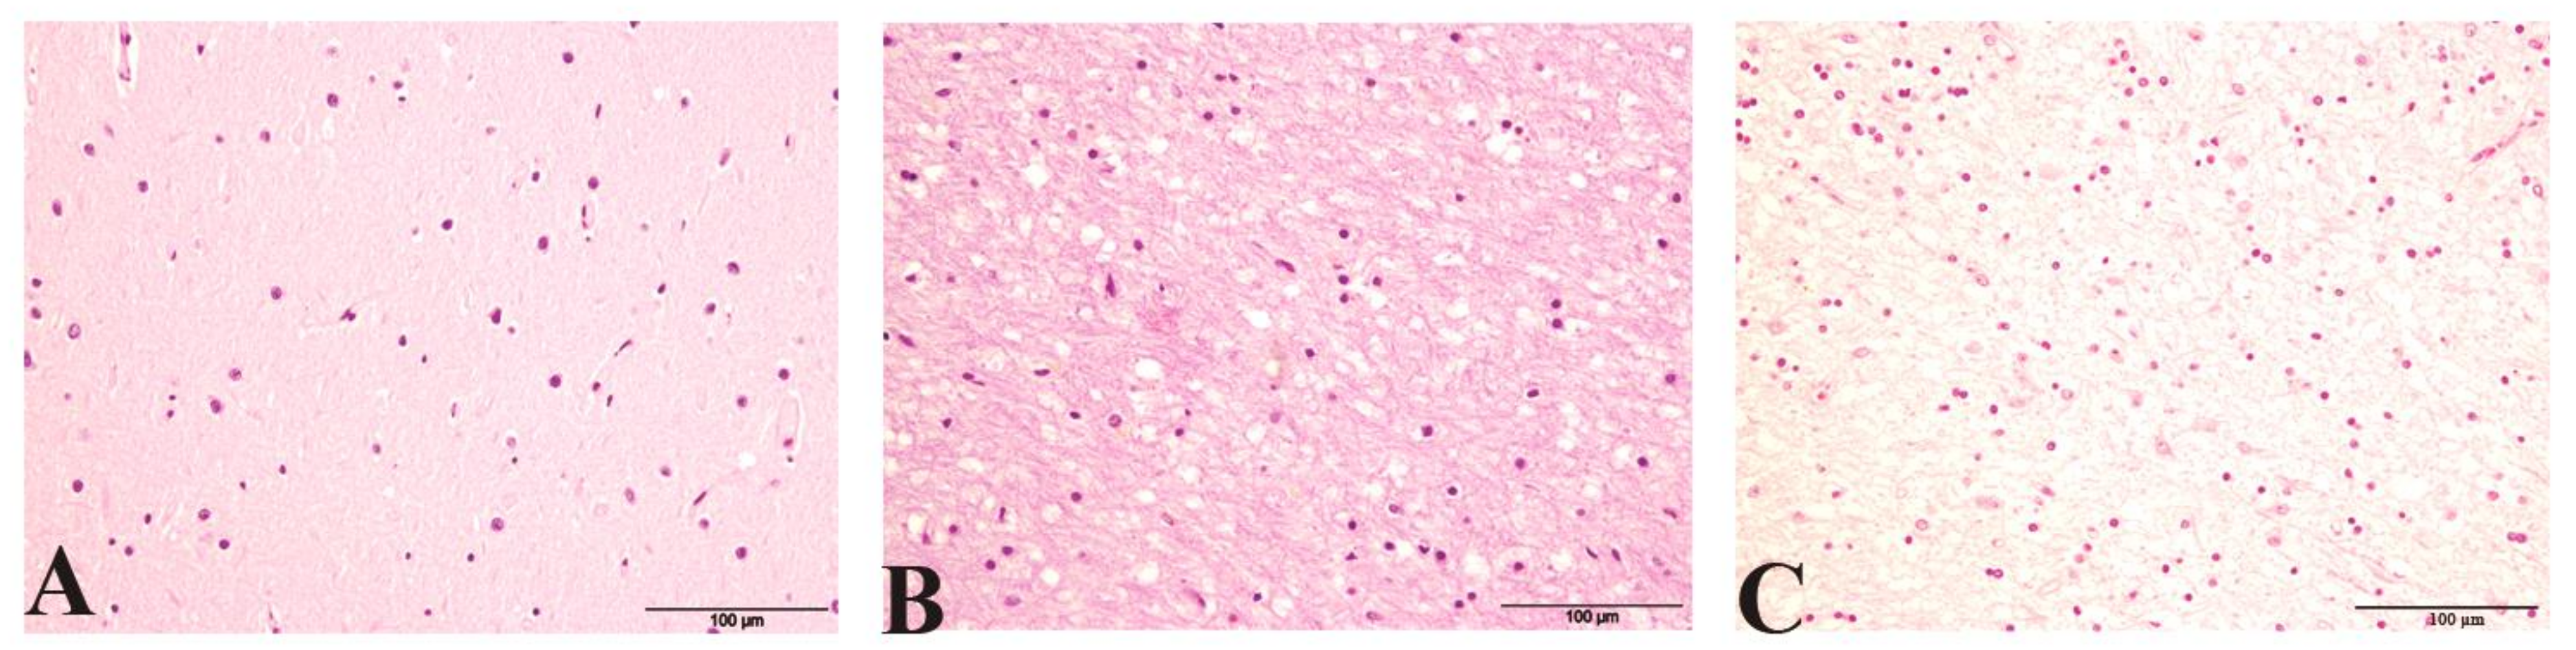

Spongiform changes were seen in all CJD samples by H/E staining but were absent in the three control cases (Figure 1). The severity of spongiform change was highly variable among cases reaching the highest severity in iCJD regardless of the brain region examined (3.08 ± 0.90 in cerebellum and 2.57 ± 0.93 in frontal cortex; Figure 2). One iCJD MM1 case showed a spongiosis status compatible with panencephalopathic cases of sCJD.

Figure 1.

Hematoxylin eosin staining (H/E) showing (A) No evidence of spongiosis in a control. (B) Typical spongiform change associated with CJD. (C) Spongiosis status compatible with panencephalopathic CJD in iCJD MM1.